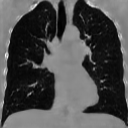

The results presented in Table 1 and 2 show our proposed method’s performance on unconditional 3D brain MR and chest CT image generation. Our proposed approach not only outperforms most comparing methods in FID and MS-SSIM metrics, it also has the lowest inference GPU memory footprint at a resolution of and was the only diffusion-based method that could be trained at a resolution of . Operating in the wavelet domain and profiting from the reduced spatial dimension also results in a relatively short inference time of / at the respective resolutions. Compared to the results presented in [23], we did not find that incorporating wavelet information into the network’s feature space (WavU-Net) increased the model’s performance. Qualitative results of our proposed method (WDM) are shown in Fig. 2 and 3. A qualitative comparison of samples produced by all evaluated methods can be found in the Supplementary Material.